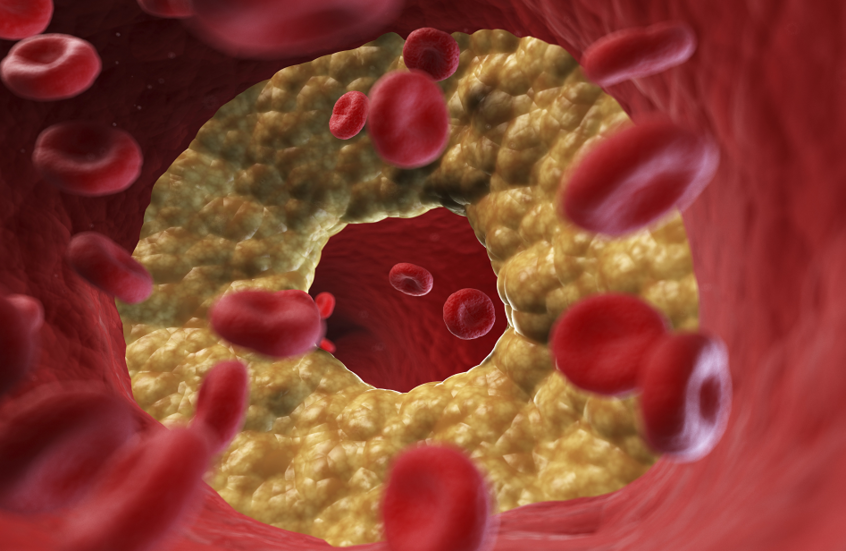

أفادت الدكتورة أوكسانا بلاتونوفا أخصائية الأشعة، أن الأشعة السينية لا تزال أداة تشخيصية مهمة، ولكن لا تزال المخاوف تحيط بها.

وتوضح الطبيبة، لماذا قد يكون رفض الفحص أكثر خطورة على الشخص من الإشعاع نفسه.

ووفقا لها، يستخدم الإشعاع فقط في أنواع معينة من الفحوصات، ولا تتضمن جميع طرق التشخيص التعرض للإشعاع. فمثلا، يستخدم التصوير بالموجات فوق الصوتية والتصوير بالرنين المغناطيسي وهذه طرق آمنة تماما حتى للنساء الحوامل. أما الأشعة السينية فتستخدم فقط في التصوير الشعاعي، والتصوير الفلوري، والتصوير المقطعي المحوسب، بينما لا تتضمن طرق أخرى التعرض للإشعاع.

وتقول: "يمكن للنساء المرضعات الخضوع لأشعة الأسنان السينية، والتصوير الفلوري، وتصوير الثدي بالأشعة السينية بأمان. ولا يؤثر الإشعاع على حليب الثدي أو الطفل. ولكن توصف الأشعة السينية للنساء الحوامل فقط في حالات طبية صارمة، وحينها يجب حماية البطن بمئزر من الرصاص".

وبالإضافة إلى ذلك، تصدر الأجهزة الحديثة جرعات ضئيلة. أي لتلقي الإشعاع الضار، يتطلب الأمر الخضوع لمئات عمليات المسح المتتالية - وهو أمر مستحيل في الممارسة العملية. وللمقارنة، تصدر أشعة الأسنان السينية حوالي 30 ميكروسيفرت، وتصدر أشعة الفلوروغرافي (fluorography) حوالي 500 ميكروسيفرت، و تعتبر الجرعة التي تزيد عن 50 ألف ميكروسيفرت سنويا خطيرة.

وتشير الطبيبة إلى أنه لا أساس من الصحة للمخاوف الشائعة بشأن مخاطر أشعة الأسنان السينية. لأن الشعاع يركز بدقة على المنطقة المطلوبة، وتغطى الأنسجة المحيطة به.

وتقول: "الأشعة السينية هي إشعاع كهرومغناطيسي، مثل الأشعة فوق البنفسجية والضوء والحرارة. صحيح قد تلحق جرعاتها العالية الضرر بالخلايا، كالذي تسببه حروق الشمس. وأن الاستلقاء تحت أشعة الشمس على الشاطئ دون حماية أخطر بكثير من تصوير بالأشعة السينية للصدر مرة واحدة سنويا".

وتؤكد بلاتونوفا، أن عدم اكتشاف المرض أخطر بكثير من الخضوع للأشعة السينية، حيث المعدات الحديثة تقلل من المخاطر، كما أن الفحوصات في الوقت المناسب تسمح بالكشف السريع عن الأمراض وبدء العلاج.